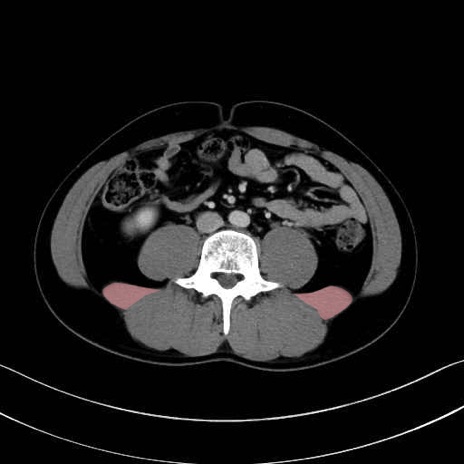

腰方形筋 (Quadratus lumborum)